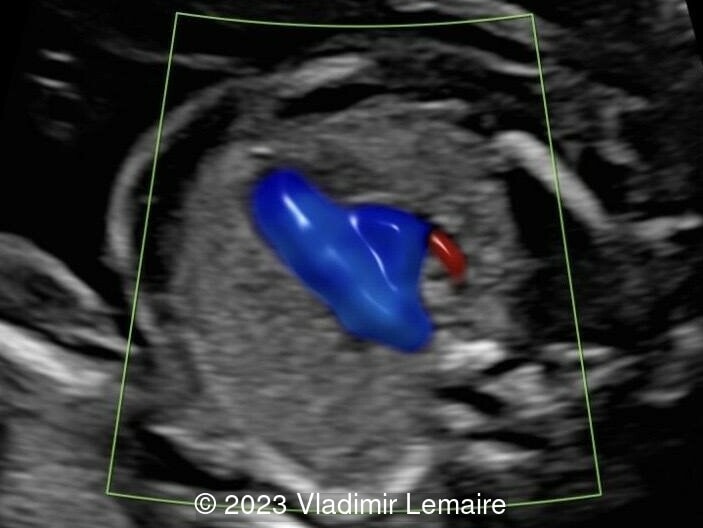

Aberrant right subclavian artery, seen in blue, in a fetus at 23 weeks of gestation.

Image 7 Aberrant right subclavian artery, seen in blue, in a fetus at 23 weeks of gestation.